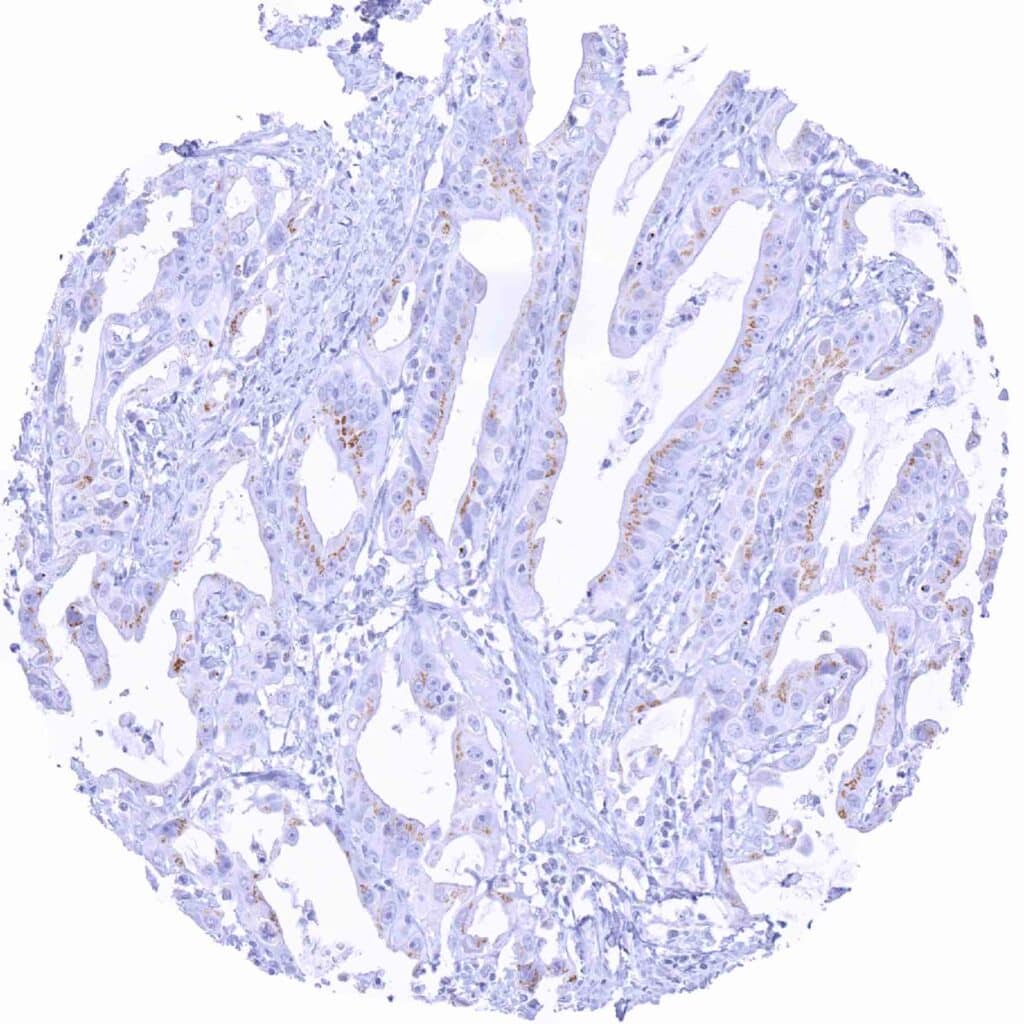

Esophagus – Adenocarcinoma showing weak, granular perinuclear Prostein staining of a fraction of tumor cells